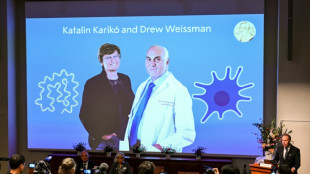

Katalin Kariko e Drew Weissman, os pioneiros do RNA mensageiro que levaram o Nobel

A persistência da bioquímica húngara Katalin Karikó e do médico americano Drew Weissman na pesquisa do RNA mensageiro celular rendeu muitos sacrifícios e alguns contratempos, reconhecidos nesta segunda-feira (2) com o Prêmio Nobel de Medicina pelo desenvolvimento de vacinas contra a covid-19.

Nobel de Medicina para os pioneiros das vacinas RNA mensageiro

A bioquímica húngara Katalin Karikó e o pesquisador americano Drew Weissman foram anunciados nesta segunda-feira (2) como os vencedores do Prêmio Nobel de Medicina de 2023 por seus trabalhos sobre RNA mensageiro (RNAm), que abriram o caminho para o desenvolvimento das vacinas contra a covid-19.

Katalin Karikó e Drew Weissman vencem o Nobel de Medicina por pesquisas sobre vacinas de RNAm

A bioquímica húngara Katalin Karikó e o pesquisador americano Drew Weissman foram anunciados nesta segunda-feira (2) como os vencedores do Prêmio Nobel de Medicina de 2023 por seus trabalhos sobre RNA mensageiro (RNAm), que abriram o caminho para o desenvolvimento das vacinas contra covid-19.